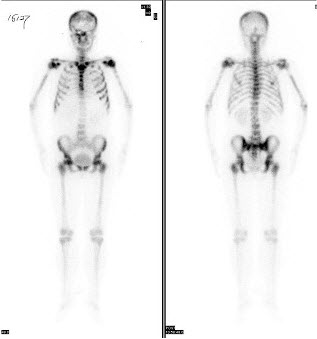

D.肥厚型心肌病

13、多项选择题

一男性病人的99Tcm-MIBI运动-静息心肌灌注显像如图,可能的诊断是()

A.左心室无心肌缺血

B.左心室前壁缺血

C.左心室心尖缺血

D.左心室前侧壁缺血

E.左心室后壁缺血

64、单项选择题

男,48岁,肺小细胞癌化疗中,诉全身疼痛,行全身骨显像如图,可能的诊断是()

A.广泛骨转移瘤

B.颅骨有冷区

C.大致正常的影像

D.颅骨有“甜面圈”征

E.是超级骨显像